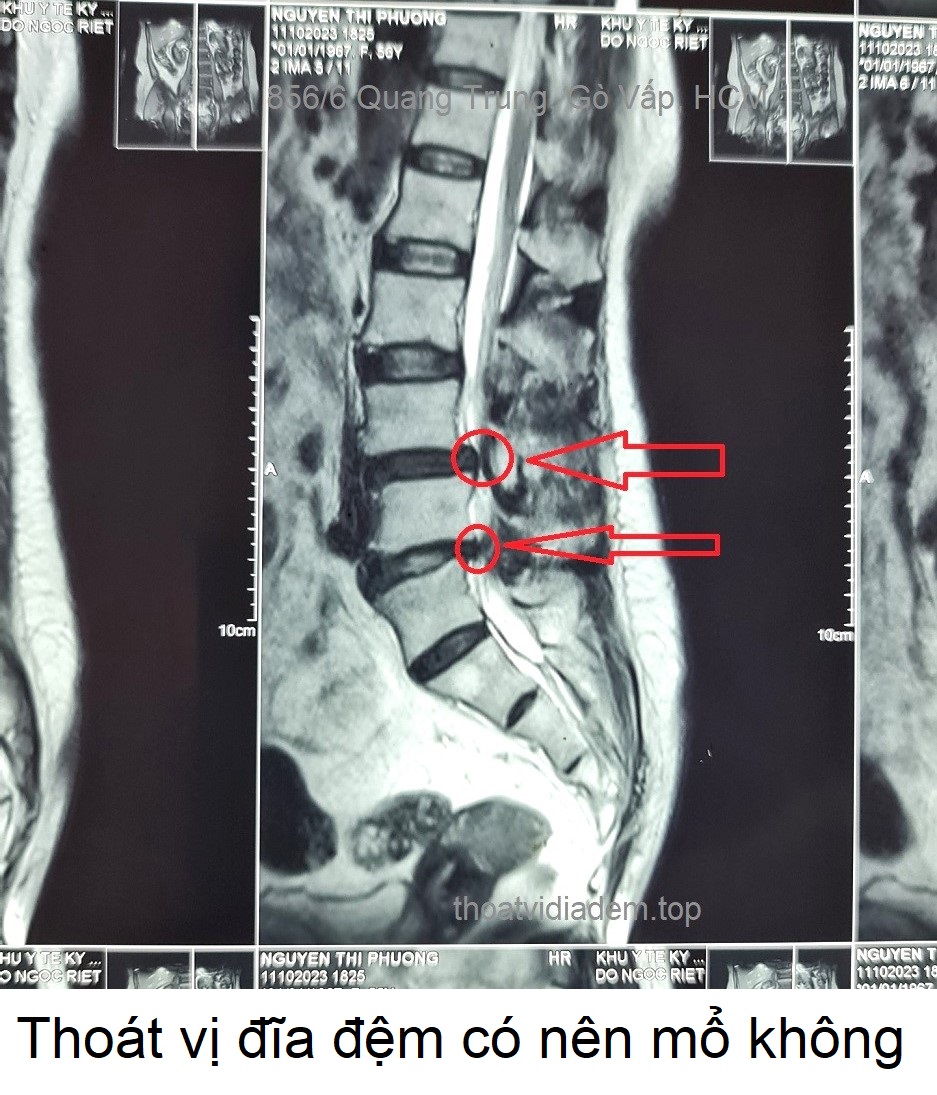

Thoát vị đĩa đệm có nên mổ không

Những người bị thoát vị đĩa đệm nặng, đã uống thuốc hoặc tiêm thuốc giảm đau không nhưng không hết đau hết nhức. Đi bệnh viện khám thì bác sĩ chỉ định phẫu thuật thoát vị đĩa đệm, họ rất phân vân lo lắng với hàng loạt câu hỏi; thoát vị đĩa đệm có nên mổ không, nếu mổ có bị biến chứng gì không, mổ rồi có hết tê nhức không. Nếu không mổ thì chữa bằng cách nào, thuốc đông y có chữa khỏi thoát vị đĩa đệm ... -